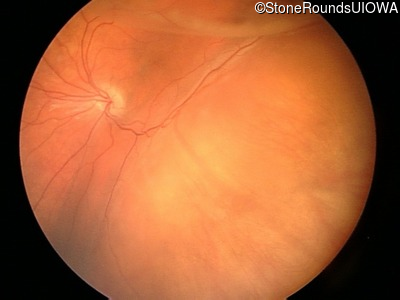

Visit at age: 3 years

Fundus Photography - Left - 20/100

Exemplar